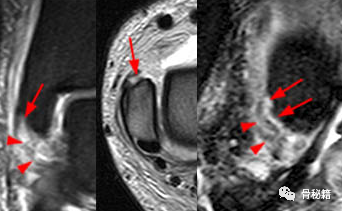

46 岁男性,一周前发生旋前外旋损伤。冠状脂肪抑制(左)、轴向 T2 加权 FSE(中)和矢状 T2 加权脂肪抑制(右)。在这种模式中,前浅表韧带最初会失效。胫舟韧带的近端(I 型)撕脱在前丘(箭头)的前缘处显示,远端韧带纤维(箭头)的边界不清、松弛和水肿明显。